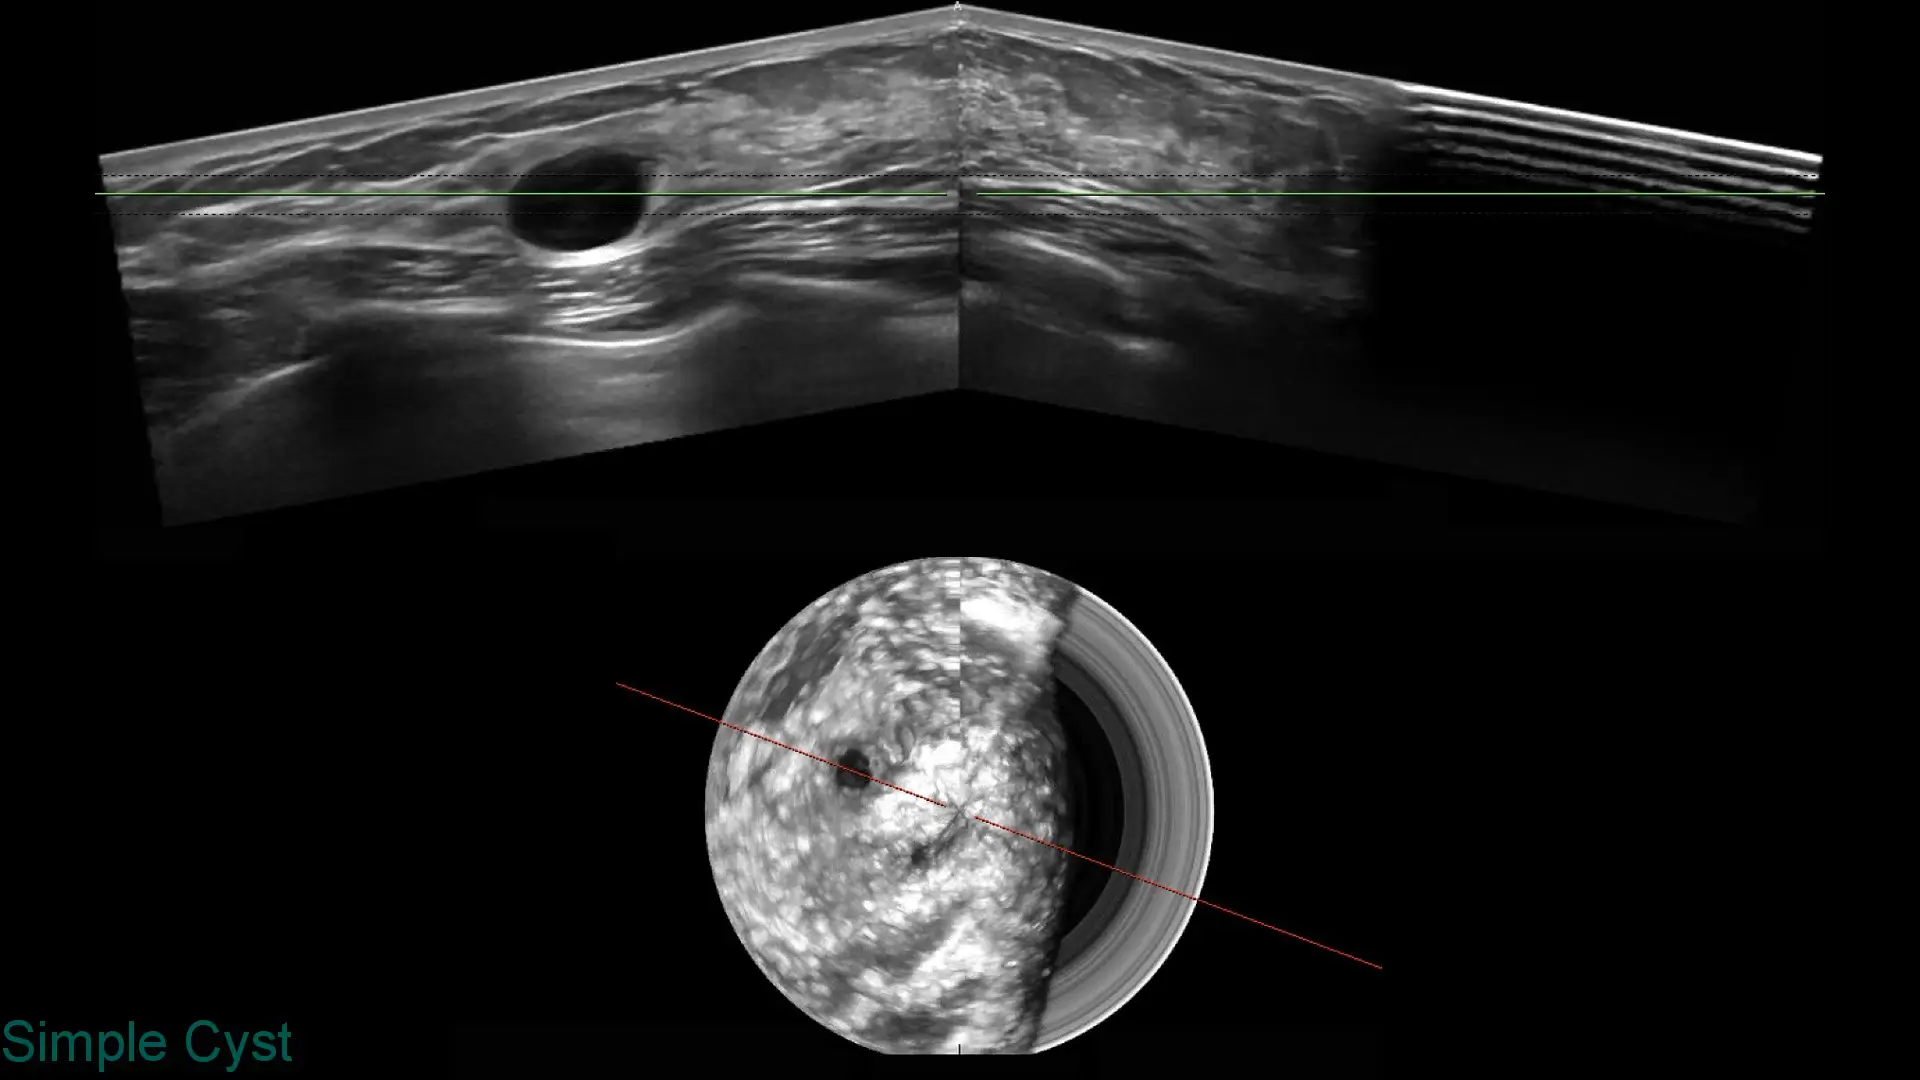

Explore clinical breast ultrasound images captured with SOFIA, showcasing various tissue types and conditions with exceptional clarity.